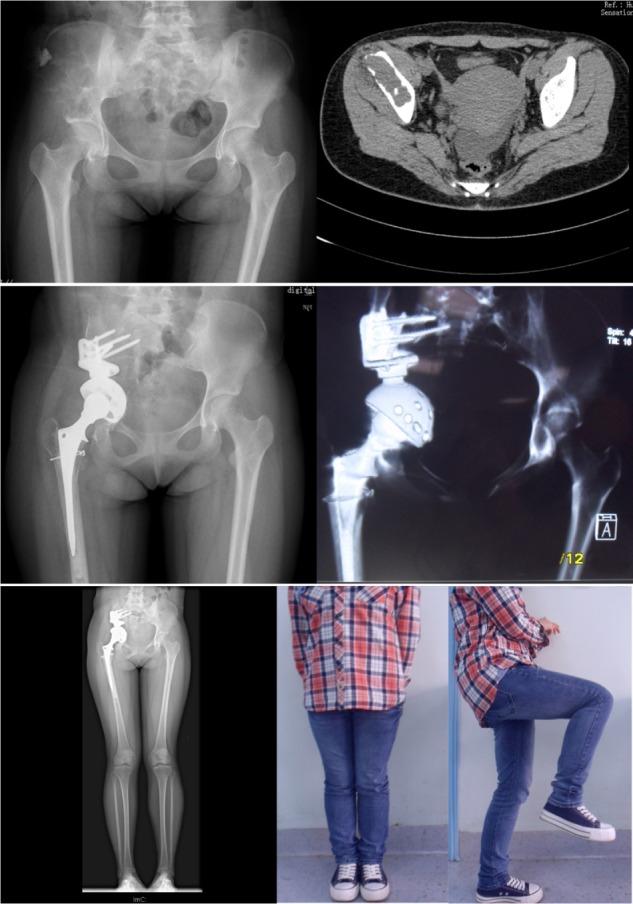

The patient, a 16-year-old girl, was admitted to our hospital with complaints of right hip pain and claudication. Her past medical history indicated that 2 years earlier she had undergone enucleation of her left eye for a primary choroidal melanoma. Imaging studies revealed a osteolytic destruction with soft tissue mass involving the right hemipelvis (zone I-II). Single-photon emission computed tomography (SPECT) and positron emission tomography-computed tomography (PET-CT) showed no other sites of metastases. Consequently, the patient underwent hemipelvic prosthesis reconstruction after tumor resection. Postoperative pathological diagnosis was metastatic malignant melanoma. Thirty months after treatment, imaging studies indicated no evidence of recurrence, and functional recovery was excellent. To our knowledge, the literature does not reveal any previously reported cases of ocular choroidal melanoma that metastasized to pelvis, meanwhile was carried out hemipelvic prosthesis reconstruction after pelvic tumor resection.

患者为 16 岁女性,因右髋部疼痛伴跛行就诊。患者既往史提示 2 年前左眼行眼内容剜除术治疗脉络膜黑色素瘤。影像学检查显示右半骨盆(Ⅰ-Ⅱ区)溶骨性破坏伴软组织肿块。单光子发射计算机断层扫描(SPECT)和正电子发射断层扫描-计算机断层扫描(PET-CT)未发现其他转移灶。因此,患者在肿瘤切除后行半骨盆假体重建。术后病理诊断为转移性恶性黑色素瘤。治疗后 30 个月,影像学检查未见复发迹象,功能恢复良好。据我们所知,文献中尚无眼部脉络膜黑色素瘤转移至骨盆并在骨盆肿瘤切除后行半骨盆假体重建的报道。